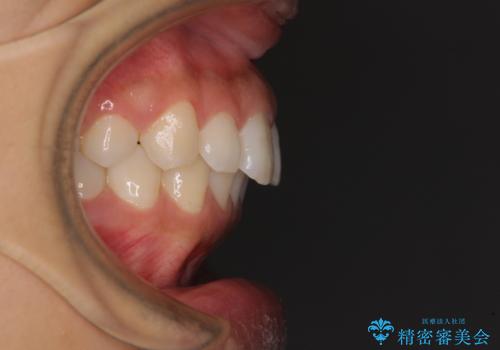

- 出っ歯で唇が閉じにくいとのことで来院された患者様です。

顎先に力を入れないと唇が閉じきれない口元であったので、上下左右の第一小臼歯4本を抜歯して、ワイヤー装置にて矯正治療を行うこととしました。

2年から2年半の治療期間を想定しており、予定通りの期間で無事に終了することができました。

唇や顎先に力を入れないなくてもスムーズに唇を閉じることができるようになりました。